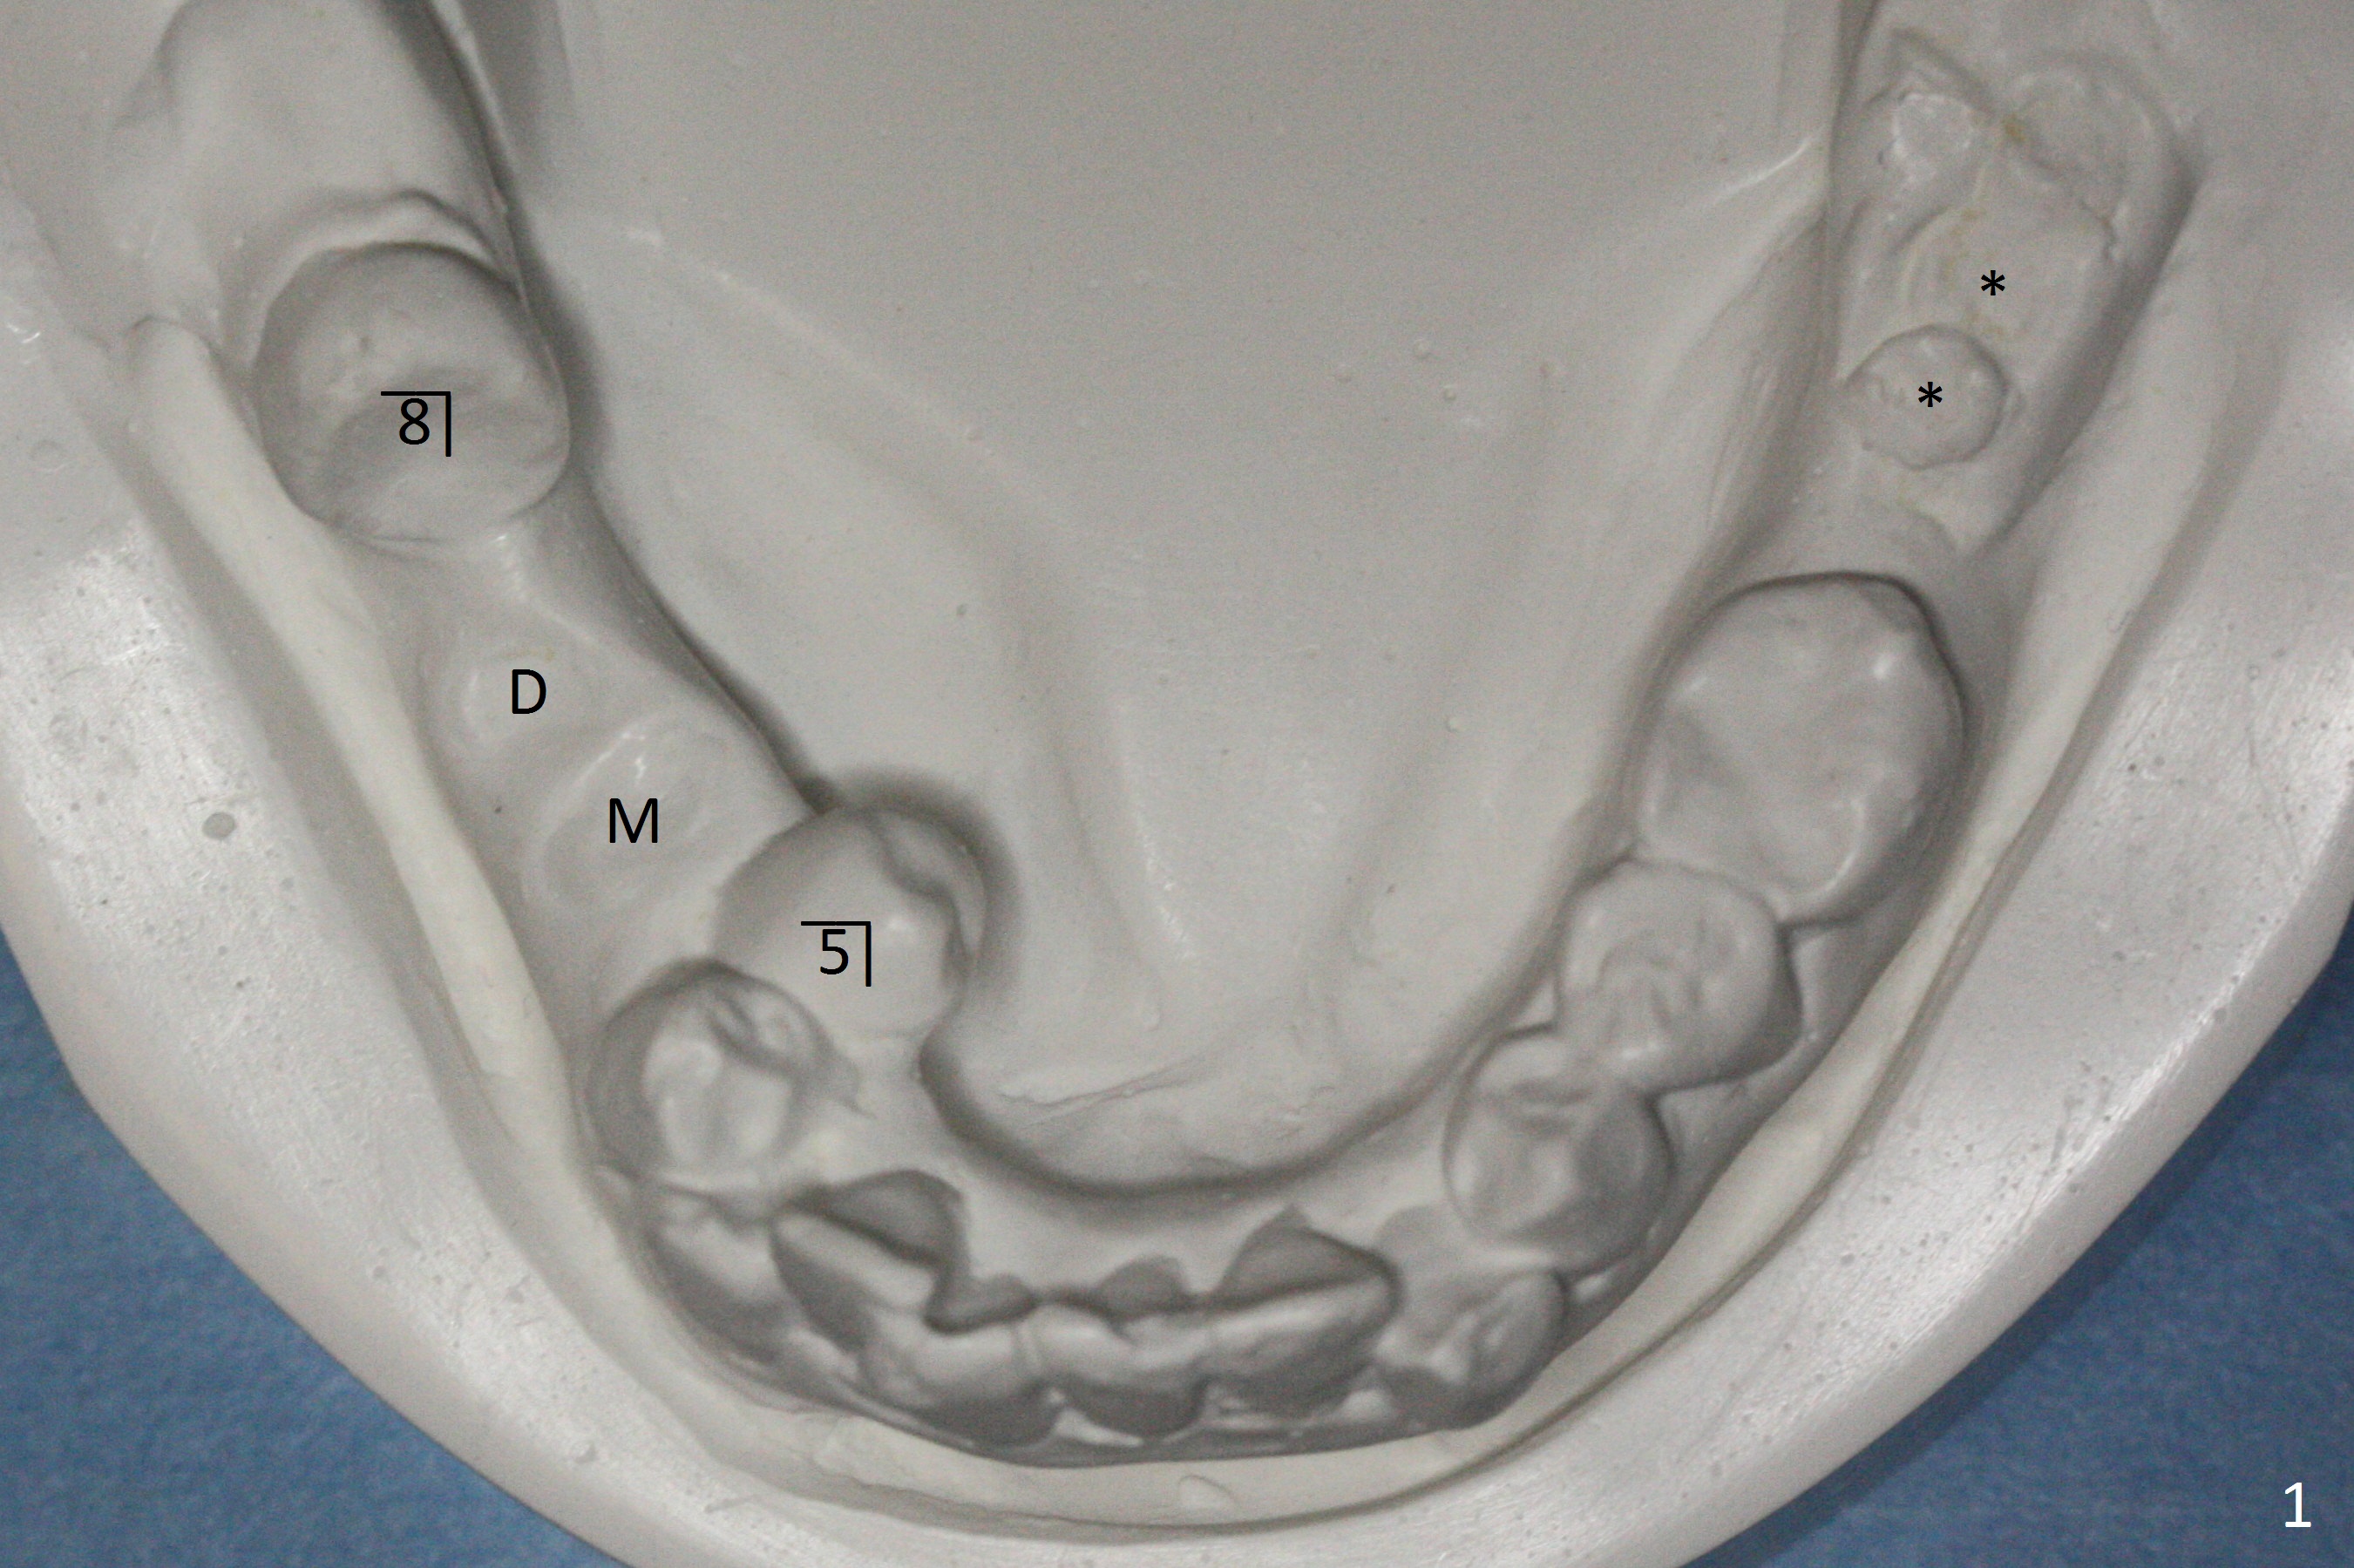

A 55-year-old woman has severe malocclusion, including linguoversion of the lower right 2nd bicuspid (Fig.1). The lower left 2nd and 3rd molars (*) and the lower right 1st molars (M (mesial) and D (distal)) have been decayed into residual root. The lower right 3rd molar is mesioangular.